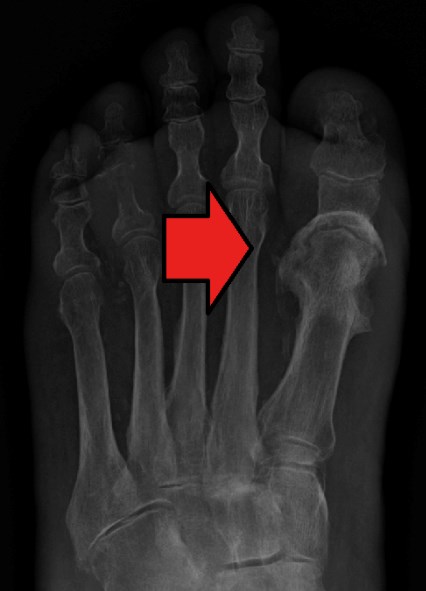

• Plain X-ray:  Useful to determine location - the most commonly affected joints in Charcot arthropathy are in the midfoot region (ie, the cuneiform/metatarsal area) [12] (Figure 22 and 23).

Figure 22: Charcot foot. X-rays of the same foot, showing progression of disease over 2 years. Fractures in the cuneiform/metatarsal area [120].

Figure 23: Osteomyelitis of the first metatarsophalangeal joint [111]